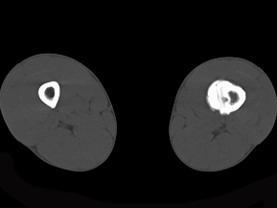

问题 患者,男,23岁,左大腿远端疼痛,夜间明显,服阿司匹林可缓解,请结合所提供图像,选择最佳答案 ( )

选项 A、骨巨细胞瘤 B、骨肉瘤 C、骨样骨瘤 D、骨化性纤维瘤 E、骨脓肿

答案 C